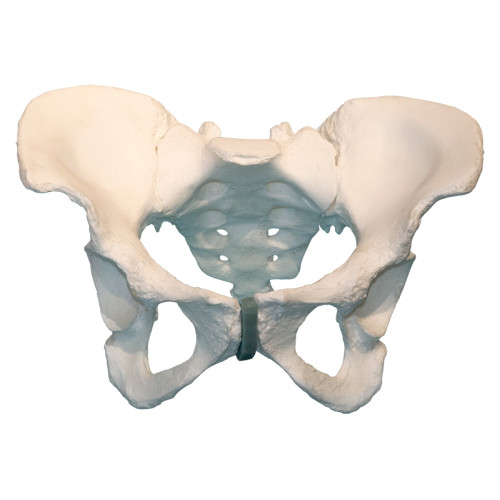

Композитная модель таза

Композитная модель таза

Описание

Модель представляет точную анатомическую копию таза человека. Путем подбора полимерных материалов механические свойства изделия (вес, плотность, упругость) максимально приближены к естественным прижизненным значениям.